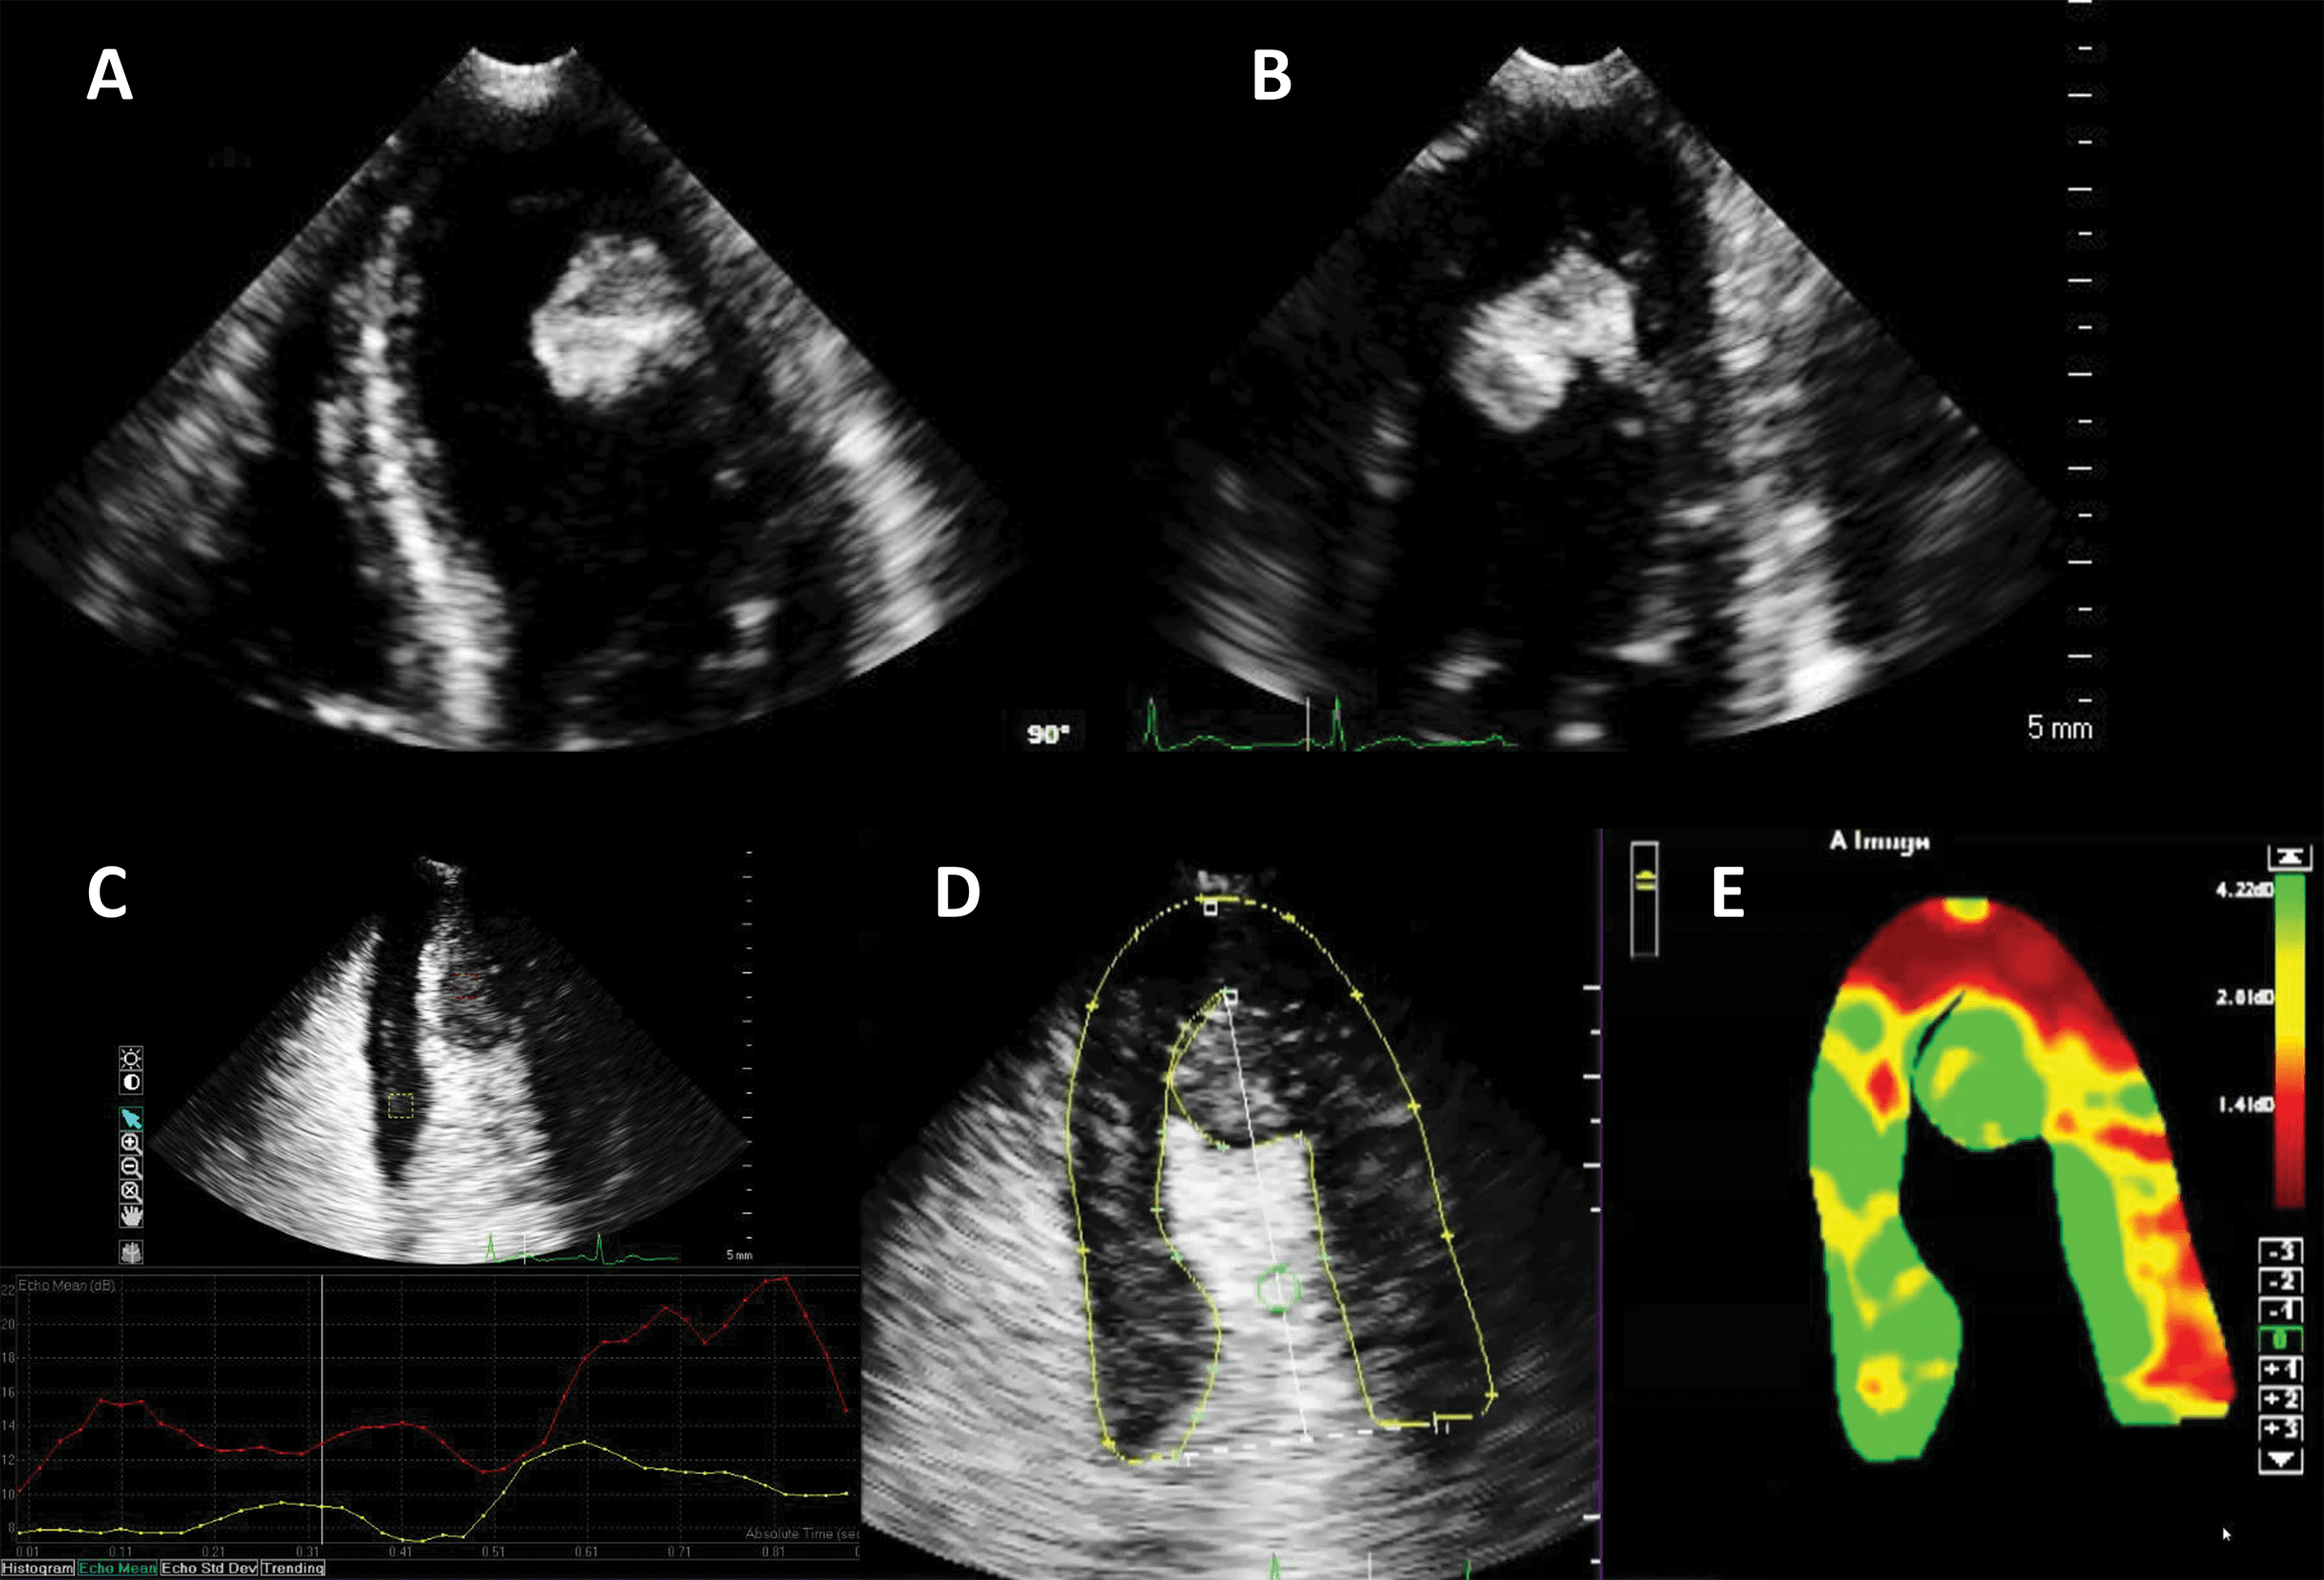

The largest body of evidence for MEE concerns the indication for LVO for enhancing the endocardial borders [10, 11, 12, 13, 14, 15]. This is achieved by using repetitive intravenous boluses of UEA, and sometimes continuous low-dose infusion. Guidelines indicate the use of LVO to enhance the endocardial borders in cases when the LV dimensions, function or regional wall motion cannot be accurately assessed using non-enhanced ultrasound [7, 14]. The general “rule of thumb” is to use microbubble UEA in cases where two or more contiguous myocardial segments are not properly visualized with non-enhanced ultrasound [13]. Of course, recent years have seen tremendous improvement in image quality for clinical ultrasound systems. But despite the introduction of harmonic imaging as a standard, some images remain non-diagnostic (Fig. 2). Moreover, harmonic imaging represented a significant leap in MEE [16, 17], leading to the present-day contrast-specific imaging modalities.

Fig. 2.Left ventricular opacification (LVO) for endocardial border delineation. Example of baseline non-enhanced echocardiography images in apical 4-chambers (A) and apical 2-chambers (B) views, where the visualization of the endocardium is suboptimal over several segments. After intravenous injection of a bolus of UEA, there is full opacification of the LV cavity, with clear delineation of the endocardium in all segments (C, D). Source: personal collection.

By using UEA, enhanced echocardiographic measurements of LV volumes and ejection fraction are very close to the reference cardiac magnetic resonance (CMR) values [11, 12], and significantly less variable as compared to unenhanced imaging, even if baseline images are of good quality [18]. This significant difference in quality, information and accuracy leads to a clinical impact on diagnosis and management [6, 19, 20]. Echocardiographic estimates of LV volume tend to be larger when using LVO, mainly because it aids the exclusion of trabeculae (Fig. 3), making the measurements closer to their CMR counterparts [13].

Fig. 3.Ejection fraction (EF) estimation. (A,B) Non-enhanced ultrasound images. The endocardium is not clearly visible in several segments (question marks), making the volumes difficult to assess. (C,D) Contrast-enhanced images. The endocardial border is clearly defined, allowing for a biplane volume estimation. Moreover, the LV end-diastolic volumes in contrast-enhanced images is notably larger than the one on the non-enhanced images, probably because of a combination of insufficient image quality on native images, and exclusion of trabeculae and papillary muscles on contrast images. Source: personal collection.